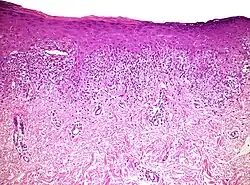

| Mycosis fungoides | Present | Focal | Regular or irregular | Normal | Normal | Minimal or no spongiosis; ±Pautrier microabscess | Atypical lymphoid cells lining the dermo–epidermal junction |  |